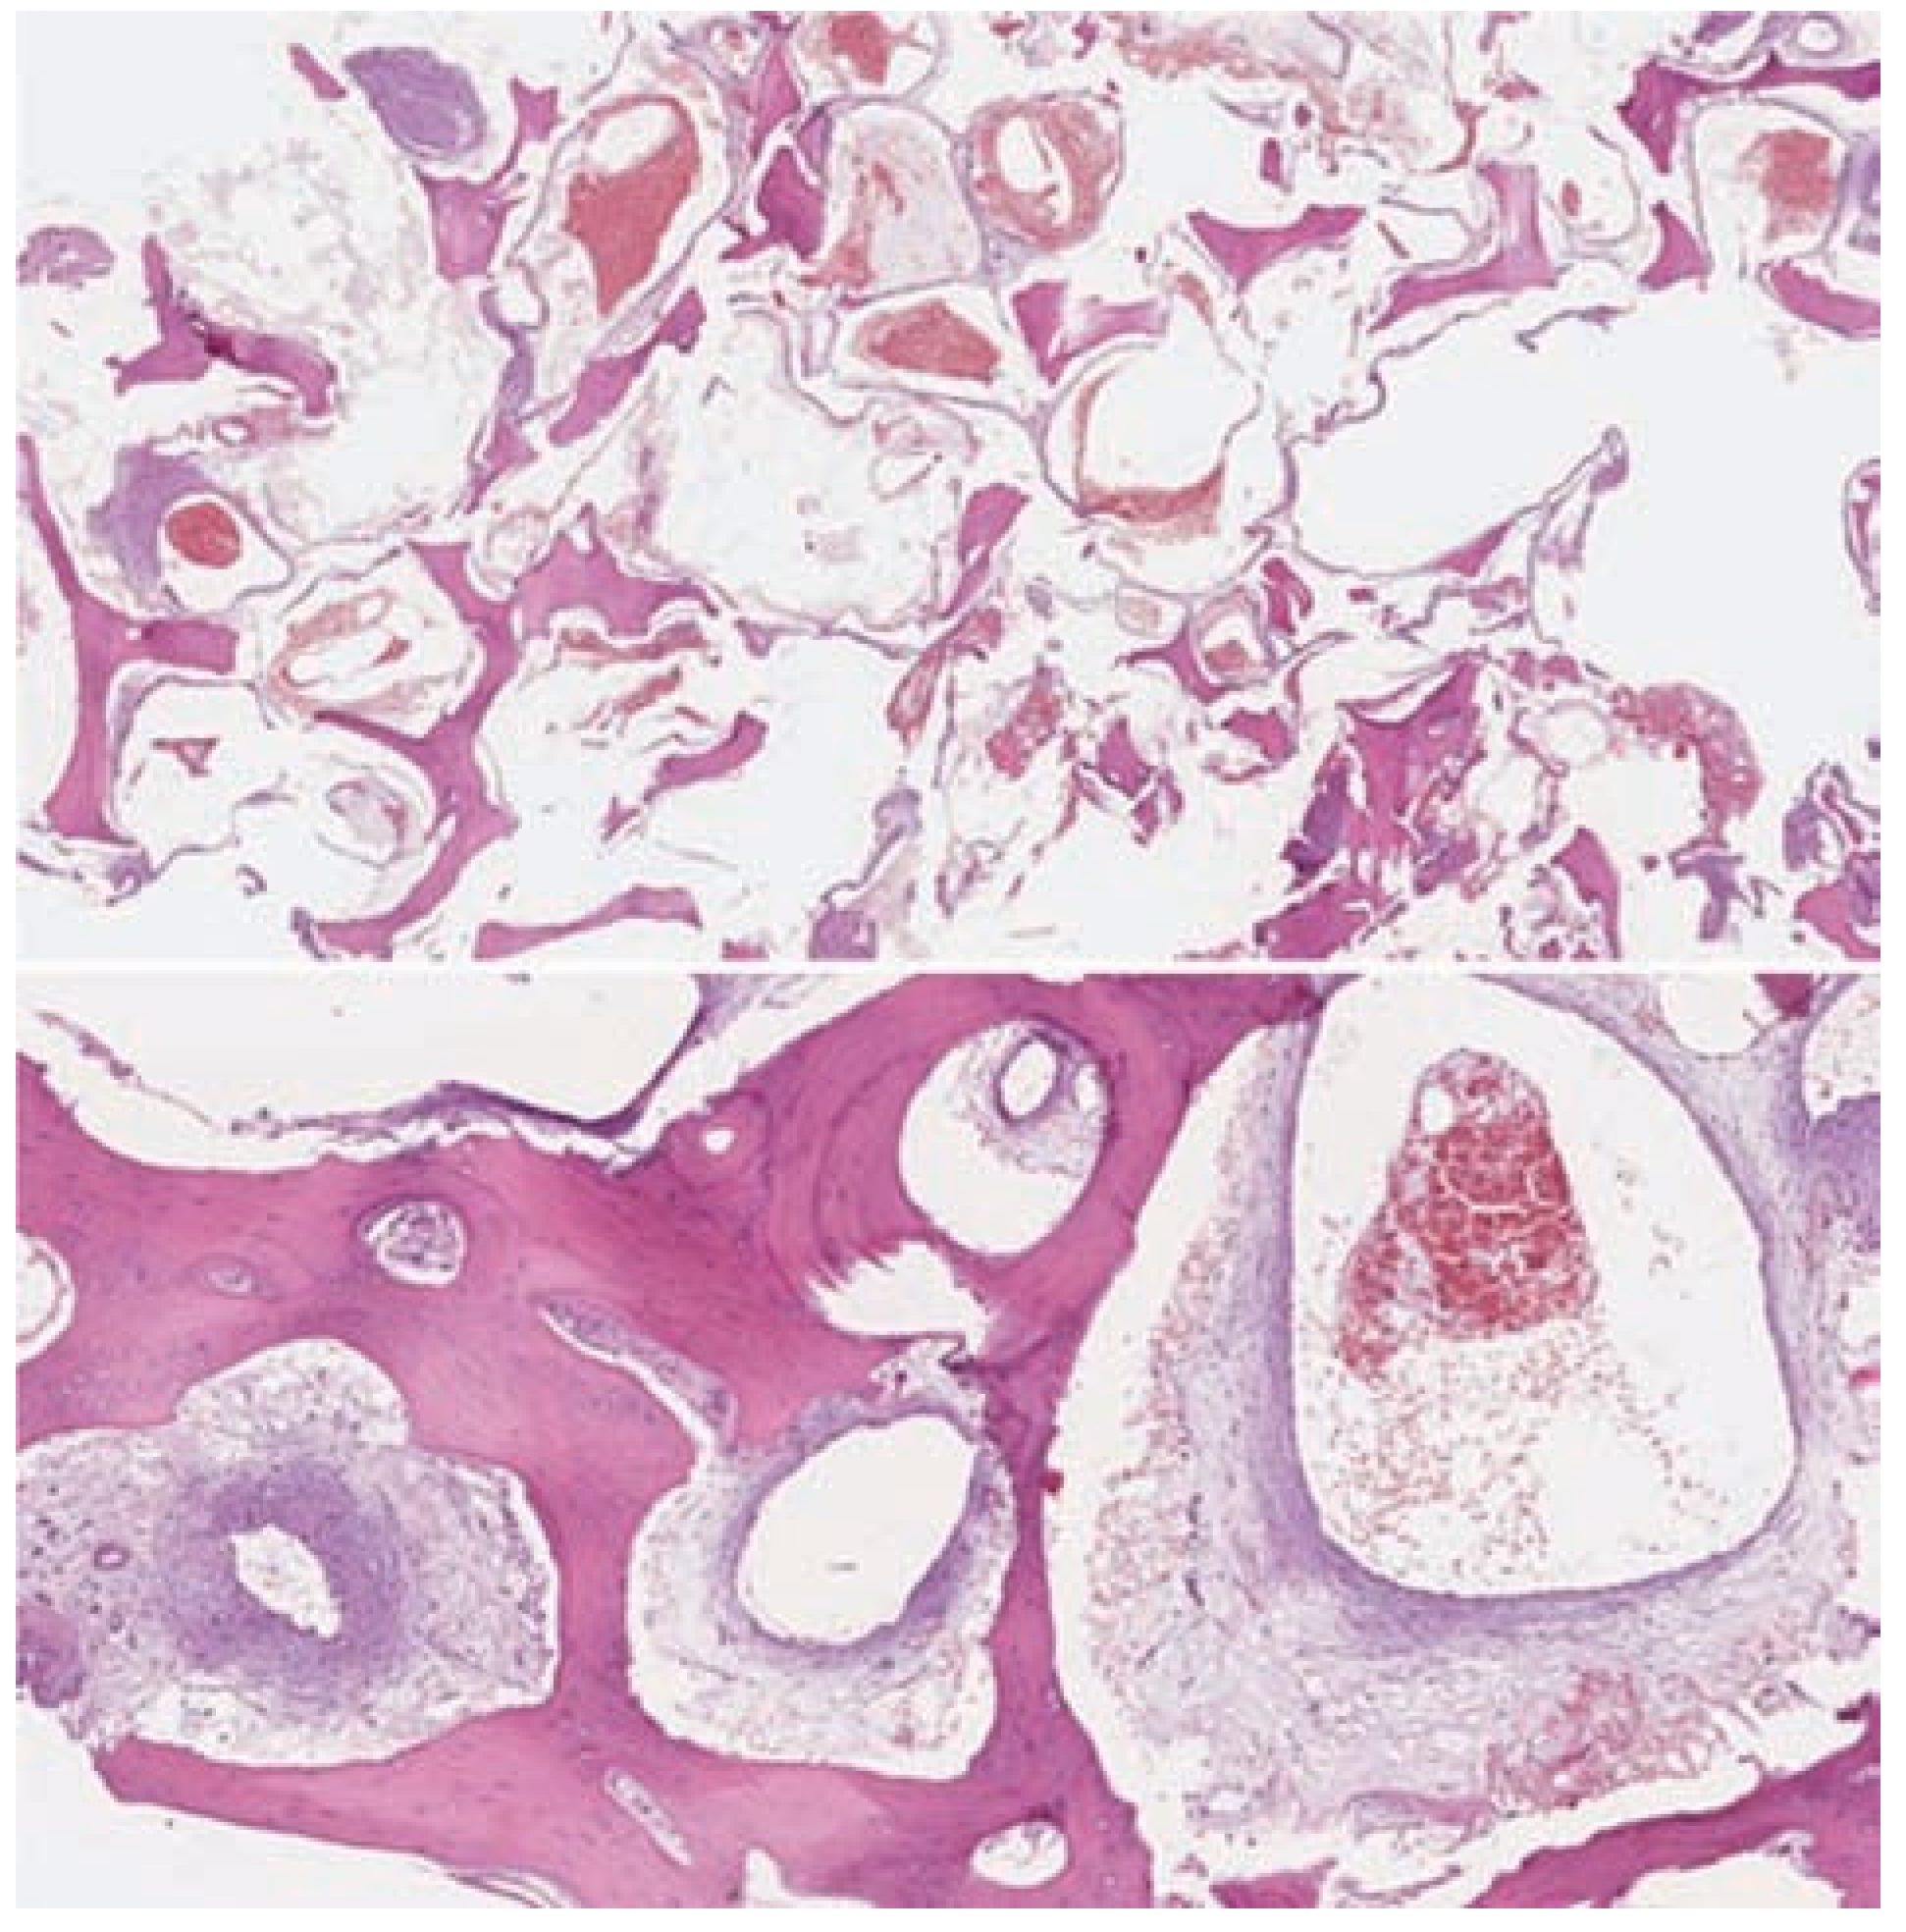

:Case Presentation

Discussion